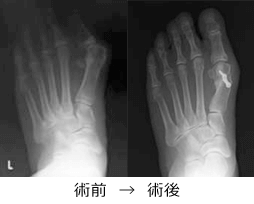

我々はレントゲンでの重症度に応じて、手術療法を行っています。手術は中足骨という骨を骨切りして足の形を整える方法です。骨切り部分はスクリューやプレートといった金属で固定します。術後早期から装具を使って歩くことが可能な手術になります。外反母趾でお困りでしたらご相談ください。